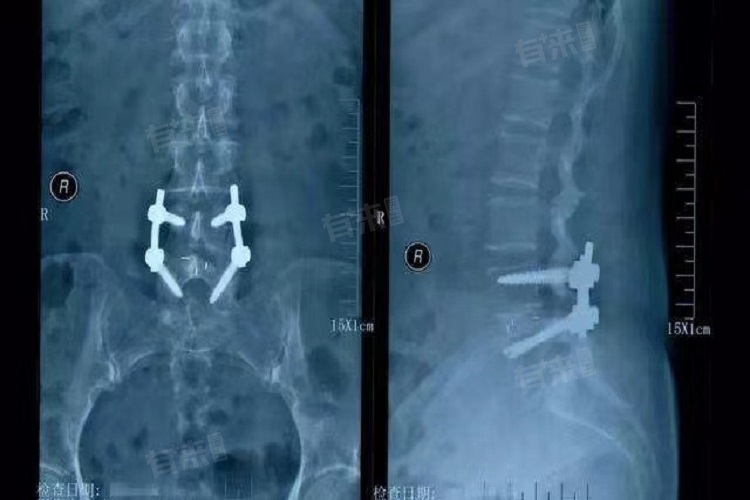

腰椎滑脱手术的费用因病情严重程度、手术方式及材料选择、地区及医院级别以及术前检查、术后护理等额外费用形成不同。一般手术费用大致在几万元到十几万元不等,具体需根据多种因素综合确定,患者在接受手术前应充分了解并咨询专业医生。

- 腰椎滑脱手术的具体方式多种多样,包括切开复位、减压术、内固定术等。不同的手术方式所需费用不同,且手术过程中所使用的材料费用也占据较大比例,如国产材料与进口材料在价格上存在差异。选择国产材料,手术费用会在几万元至十万元不等;选择进口材料,费用会更高,达到十几万元甚至更多。